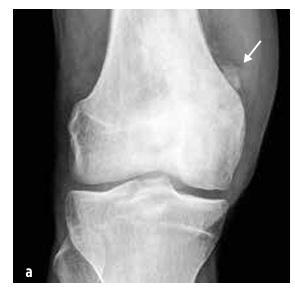

Osteosarkom distálního femuru

Obrázek č.6

Ewingův sarkom postihující skelet pánve